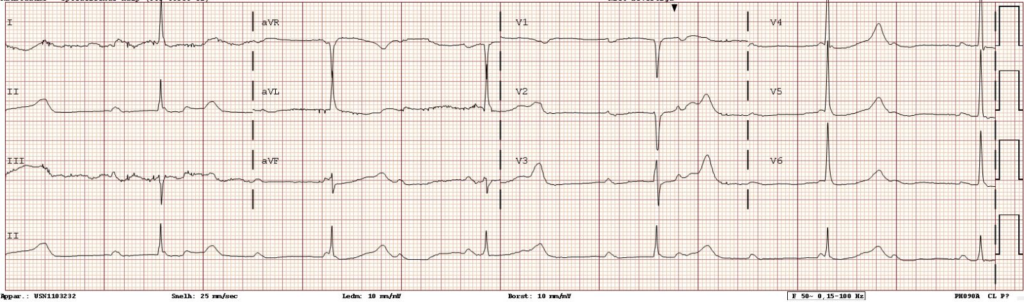

Figuur 1: ECG bij opname